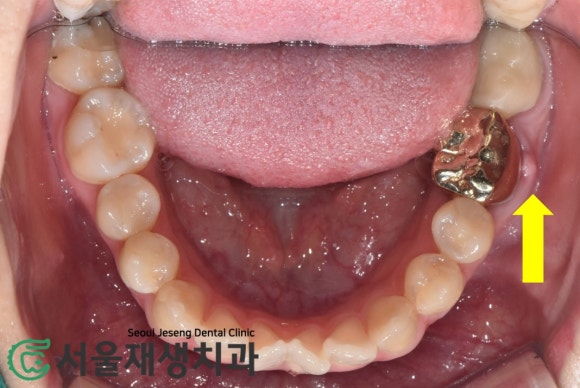

위에서 보니 더욱 확연합니다.

여드름이 나왔다는 것은

염증의 사이즈가 상당하다는 뜻입니다.

반면 내부 압력은 해소되어

통증은 없는 상태지요.

봉긋 올라왔다 터지기를 반복하는

잇몸 여드름,

통증이 없다고 방치하지 마시고

꼭 치과보존과 전문의의

검사를 받으시길 권합니다!